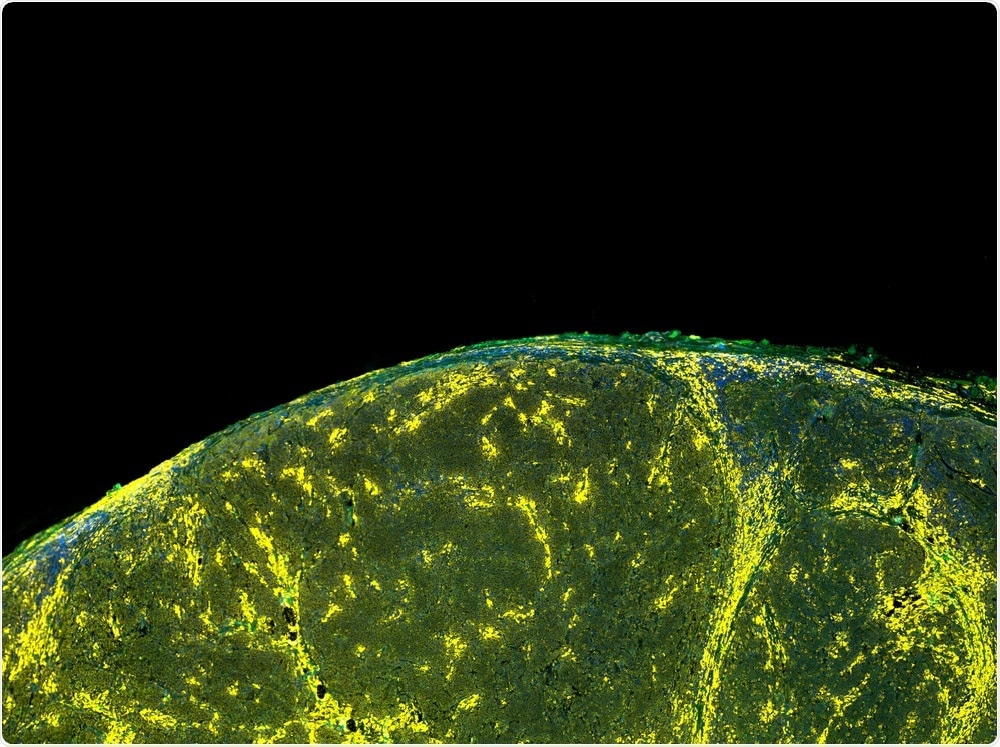

Wei Min imaging